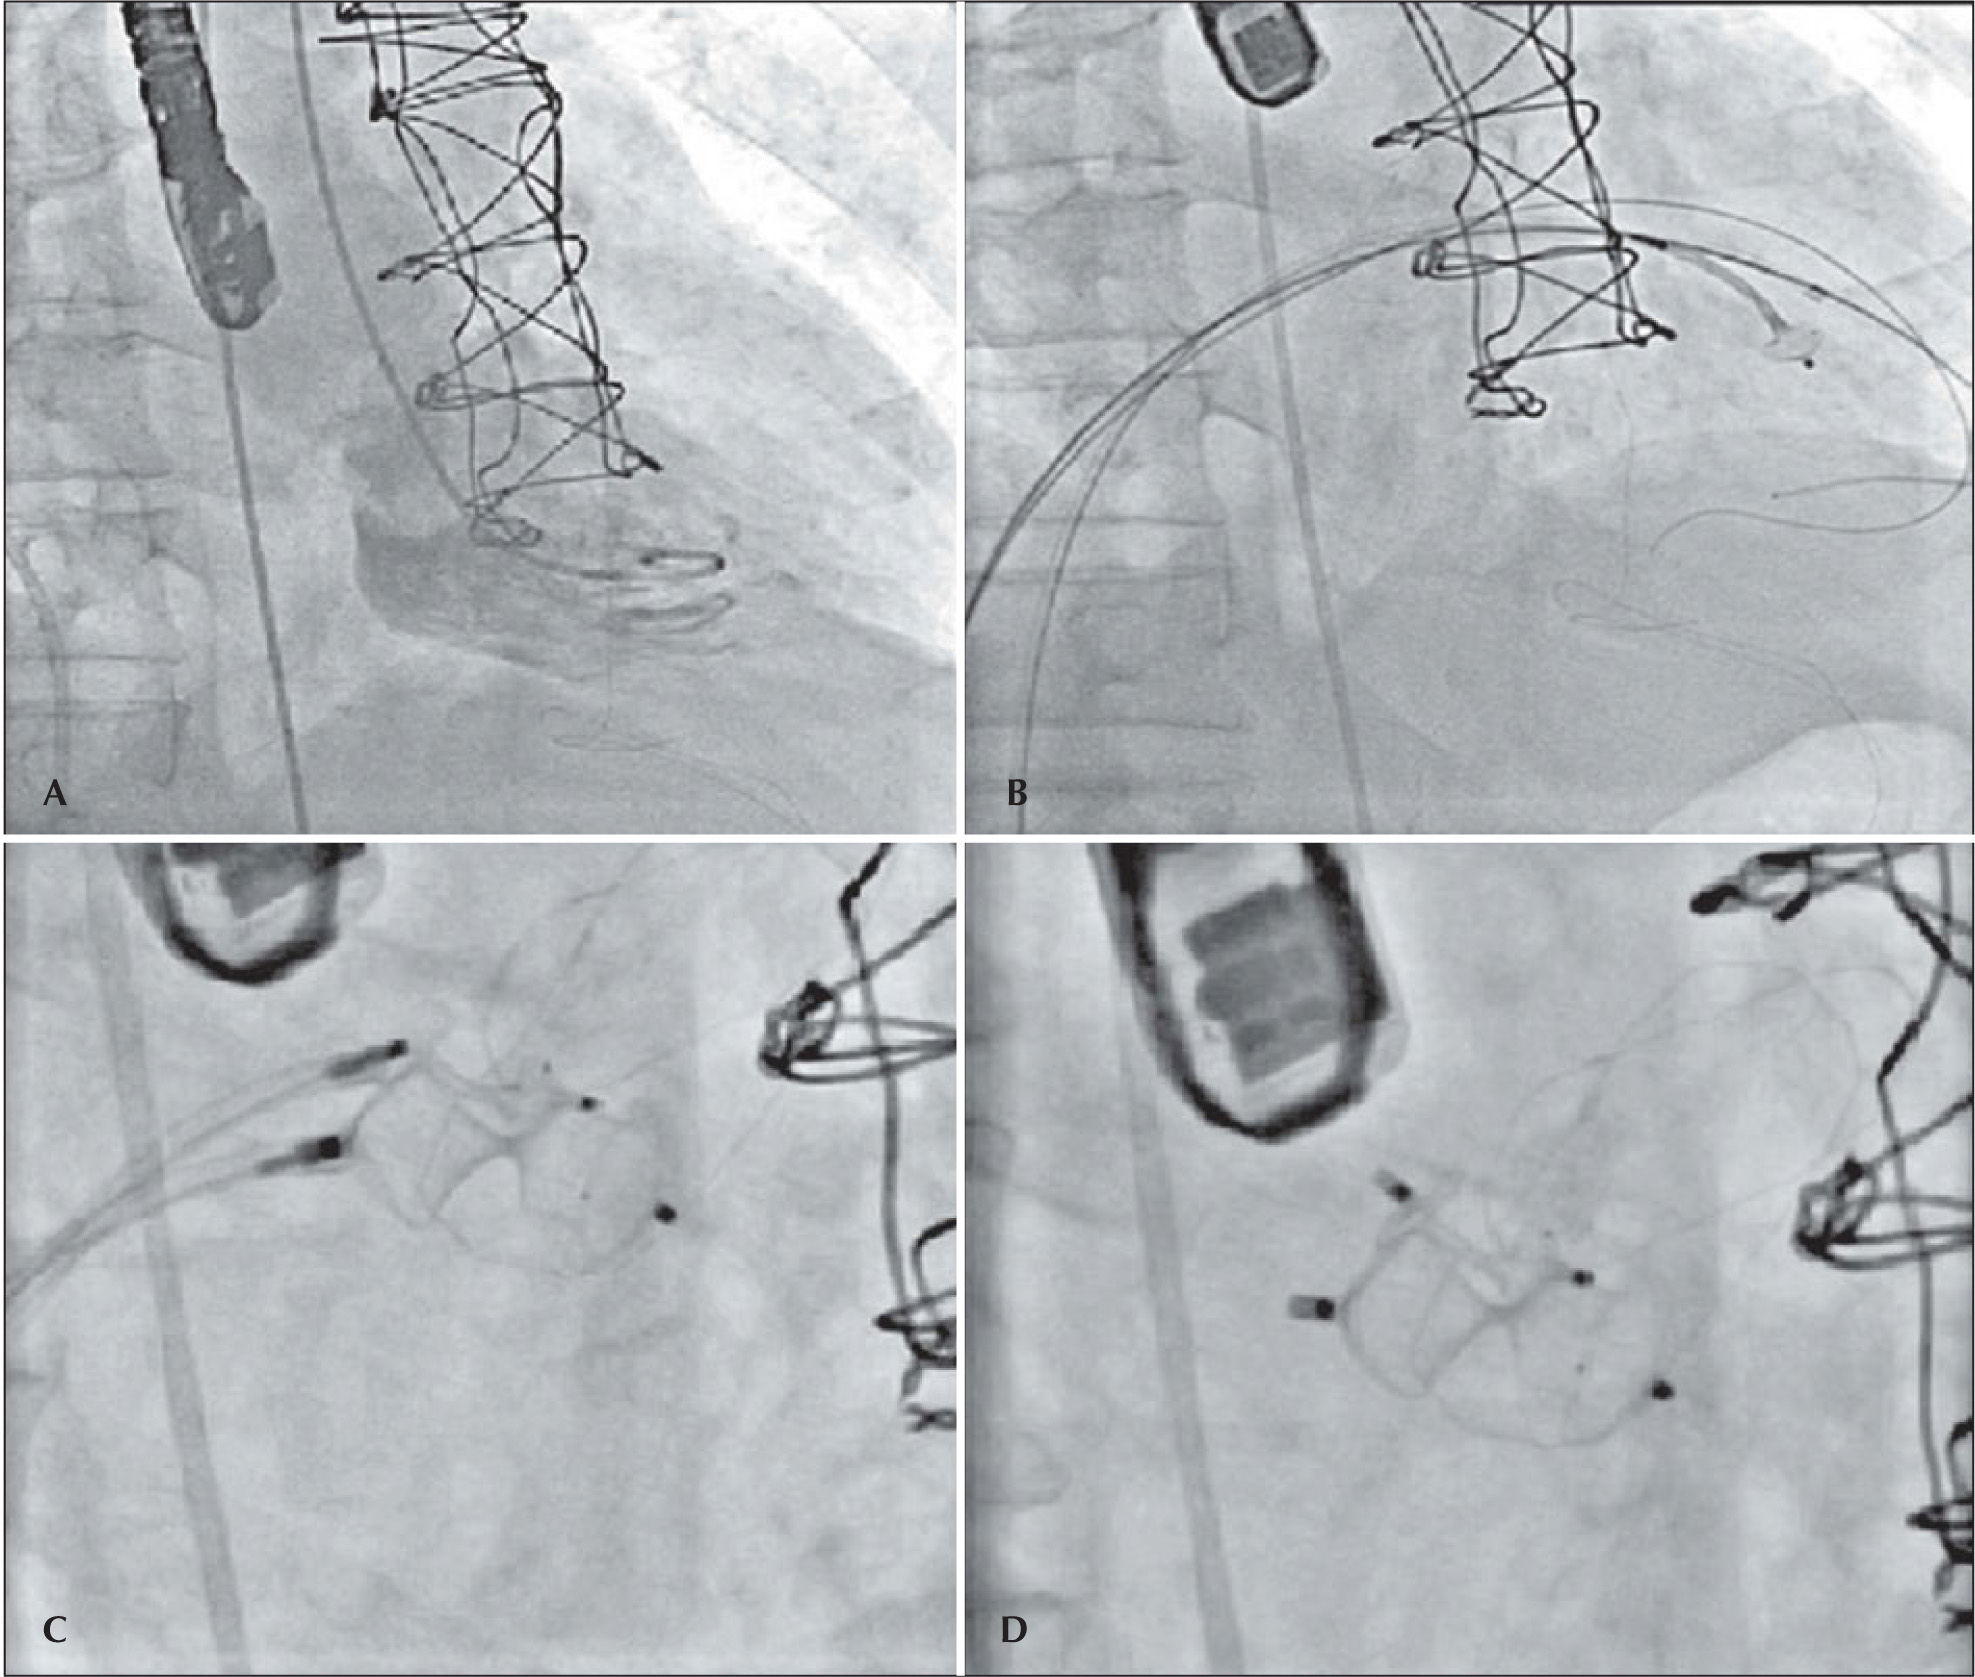

The patient developed dyspnea upon exertion, and a 2D transthoracic echocardiography was performed on November 18, 2011, which showed an ejection fraction of 60%, aortic bioprosthesis with thin leaflets without regurgitation (valve area of 1.7cm2 and maximum systolic gradients of 18mmHg, mean 10mmHg), mitral bioprosthesis with thin leaflets, preserved opening and mobility, and severe anterior paravalvular regurgitation, with maximum diastolic gradients of 13mmHg (mean 7mmHg) and slight tricuspid regurgitation. As a result of relevant symptoms and high surgical risk, a percutaneous closure of the mitral paravalvular defect was indicated and performed on November 30, 2011 (Figure 2). The procedure was performed under general anaesthesia and was initiated by puncturing the right femoral vein and the left femoral artery with 7F and 6F introducers, respectively, followed by administering a dose of 100 U/kg of unfractionated heparin. Left ventriculography was performed in the right anterior oblique projection, which showed increased end-diastolic volume and moderate inferobasal hypokinesia, as well as mild hypokinesia in the other left ventricular walls. Subsequently, a transseptal puncture was performed with a Brockenbrough needle and an 8F Mullins sheath. The paravalvular orifice was located and a 260-cm, 0.035-inch extra-stiff guidewire was introduced past it together with a 3.5, 6F Judkins right catheter curve (Johnson & Johnson Co. – Miami, FL, USA) and another similar guide with a Multipurpose 7F catheter, with the aid of 3D transesophageal echocardiography. Then, two Amplatzer™ Vascular Plug III (numbers 10–5 and 4–2) prostheses were implanted with the help of 3D transesophageal echocardiography, which was used to guide the correct positioning of the prosthesis (Figure 3). At the end of procedure, it was demonstrated that the paravalvular defect had completely disappeared (Figure 4). There were no complications during the procedure. The patient was extubated in the catheterisation laboratory and kept under observation for two hours, before discharge to the infirmary.

– In A, ventriculography in right anterior oblique view, showing mitral paravalvular regurgitation. In B, catheters in the left ventricle after moving past the mitral paravalvular orifice to start the prosthesis positioning. In C, the positioning of the prostheses and their release. In D, the final result.